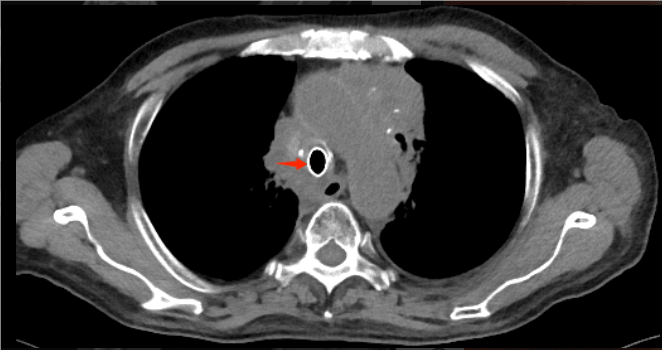

術后復查胸部CT見氣道通暢